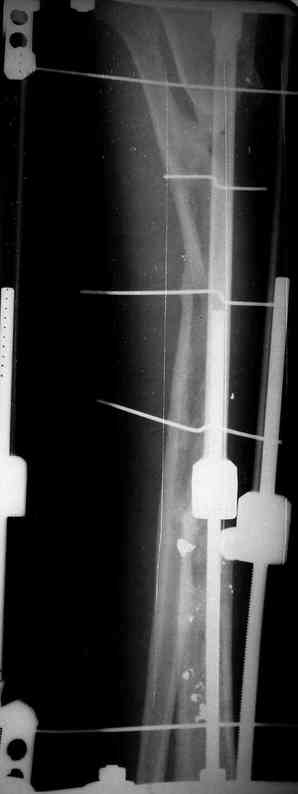

Я думал, что в нижнем отделе голени без мягкотканнего покрытия будет сложно проведения тибиализацию, но твой пример показывает - метод работает даже в таких трудных условиях.

Правда те мои случаи были сделаны давно, еще в Латинской Америке, и конечно качество исполнения отстает от идеалов, но, несмотря на отсутствие нормальных спиц с упором, метод сработал в свое время.